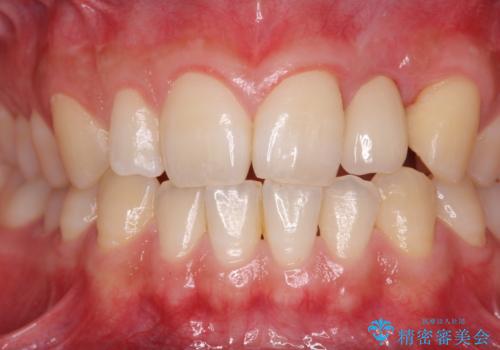

前歯部 インプラント治療

- 前歯の永久歯が元々なく、乳歯を失ったタイミングで前歯の審美性の回復を求めて来院されました。

機能・審美性の回復手段として、インプラント治療・ブリッジ・部分床義歯が考えられます。

それぞれの治療に特徴がありますが、取り外しの必要がなく隣の歯を削る必要も必要ないインプラント治療を選択されました。

前歯部にインプラントを埋入し、きれいに仕上げるためには骨の造成技術や歯肉の厚みを増すような処置を行い、インプラント周囲の環境を整備することが肝要です。